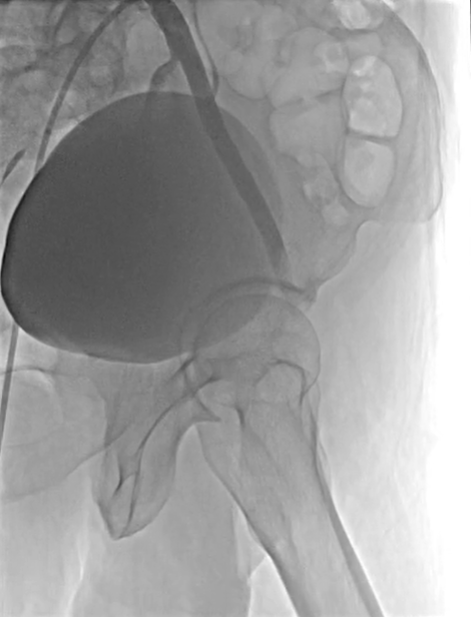

手术当天,在局部麻醉下行下肢动脉造影,提示股浅动脉近端形成无残端闭塞,闭塞长度达惊人的 40 cm,这就意味着全程都需要「摸着石头过长江」。由于闭塞长度过长且复杂,杨征副主任医师果断启动 DSA 及超声导引双指引确保手术安全性。

在功能科王艳夏医师的辅助下,手术团队与导管室李锐主管护师、鱼祥护师通力合作,同时建立正向、逆向通路,使用多种心脏泛血管技术最终应用 TIP-IN 成功双向「会师」,面对「坚如磐石」的病变,将仅有头发丝粗细的导丝顺利通过靶病变到达远端动脉血管。沿导丝送入旋切系统,导管前端的高速旋转刀片如同「微型隧道盾构机」,精准地将血管内的斑块粉碎并同步抽吸出体外。后顺利置入下肢动脉药物球囊两枚进行双保险,大大降低血管出现再狭窄概率。整个过程耗时 6 小时,40 cm 的超长闭塞的血管成功恢复了通畅血流。(术者:杨征。助手:李臻、何涛志)